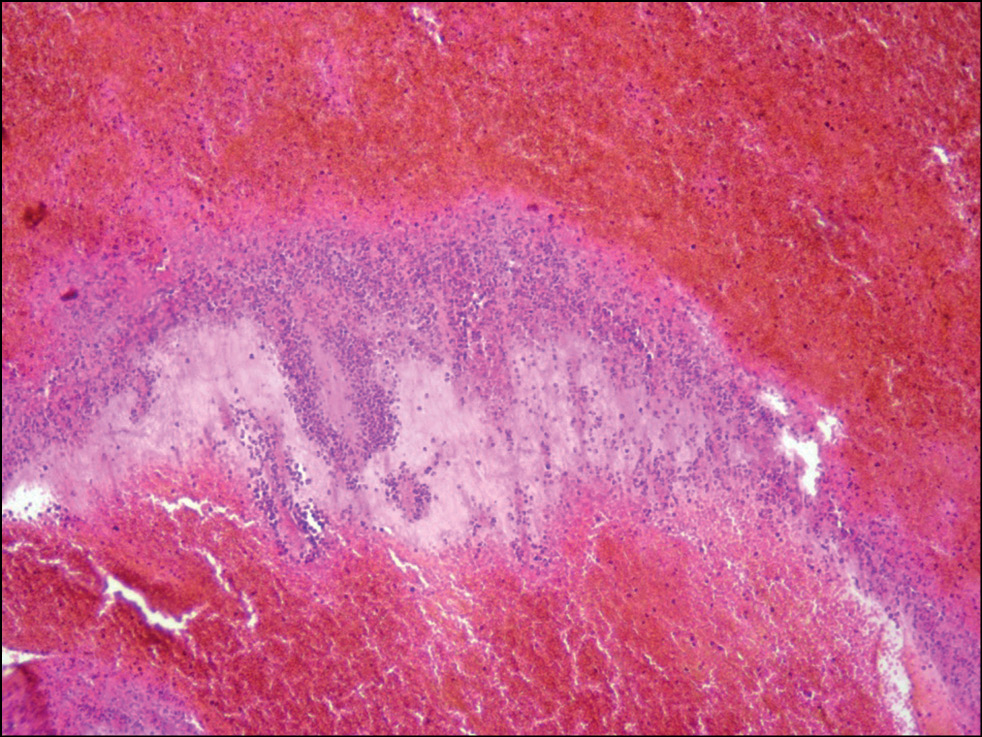

С помощью гистологического исследования установлена давность СДГ у лиц, скончавшихся до оказания медицинской помощи. В 65% случаев видимых реактивных изменений в СДГ не установлено, что могло соответствовать возрасту её образования менее 1 часа. В 20% случаев реактивные изменения соответствовали временному интервалу возраста СДГ от 12 до 24 часов (рис. 1), в 15% случаев ― от 24 до 48 часов (рис. 2).

Рис. 2. Свёрток крови под твёрдой мозговой оболочкой с установленной давностью 24–48 часов. Окраска гематоксилином и эозином, ×400.

Fig. 2. Blood coagulation under the dura mater with an established prescription of 24–48 hours. Coloring: hematoxylin and eosin, ×400.

На сегодняшний день известно, что в первые 12 часов травмы происходит начальное отложение фибрина и полиморфноклеточная миграция в свёрток со стороны его дуральной поверхности. От 12 до 24 часов в гематоме определяются начальная миграция фибробластов и фагоцитоз эритроцитов. Новообразованная мембрана визуализируется ориентировочно через 4 дня, отчётливой она становится к 10-м суткам. Неоваскуляризация отмечается не ранее чем через 5 суток. Определение калибра новообразованных сосудов при этом может вызывать трудности, поскольку этот критерий субъективен и не стандартизирован. Стоит отметить также, что толщина новообразованной мембраны должна анализироваться только относительно объёма гематомы. Если данные о размере и объёме сгустка неизвестны, то толщину неомембраны не следует брать во внимание при установлении давности СДГ [8].